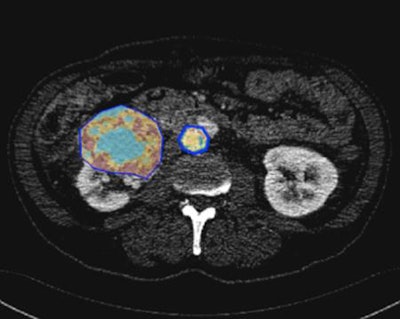

In this image, the tumor is segmented to define a region of interest in which radiomics parameters are calculated. All images courtesy of Dr. Laure Fournier, PhD."Radiomics is increasing efficiency in research using high throughput techniques and that's why we should do it. But we must understand the physics of it," she noted.